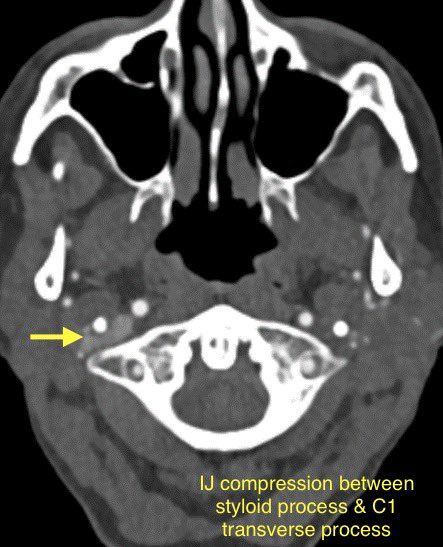

🔷OTHER CAUSES OF VENOUS PULSATILE TINNITUS

1️⃣Jugular vein outflow obstruction by the styloid process (common incidental finding in asymptomatic patients)